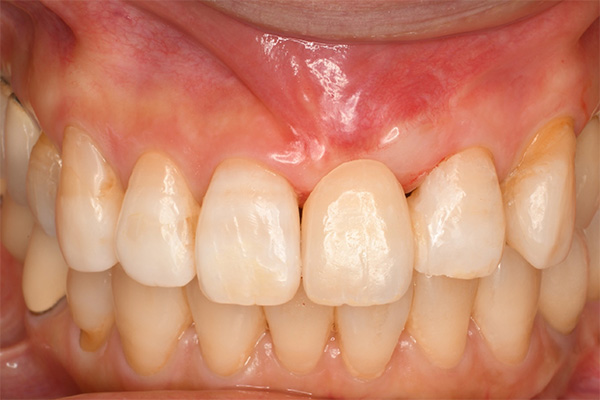

抜歯9ヶ月後(左)歯肉にヘコみができているので手術で歯肉を増大させる

2週間後、赤みは残るが歯肉の厚みは増えた(右)